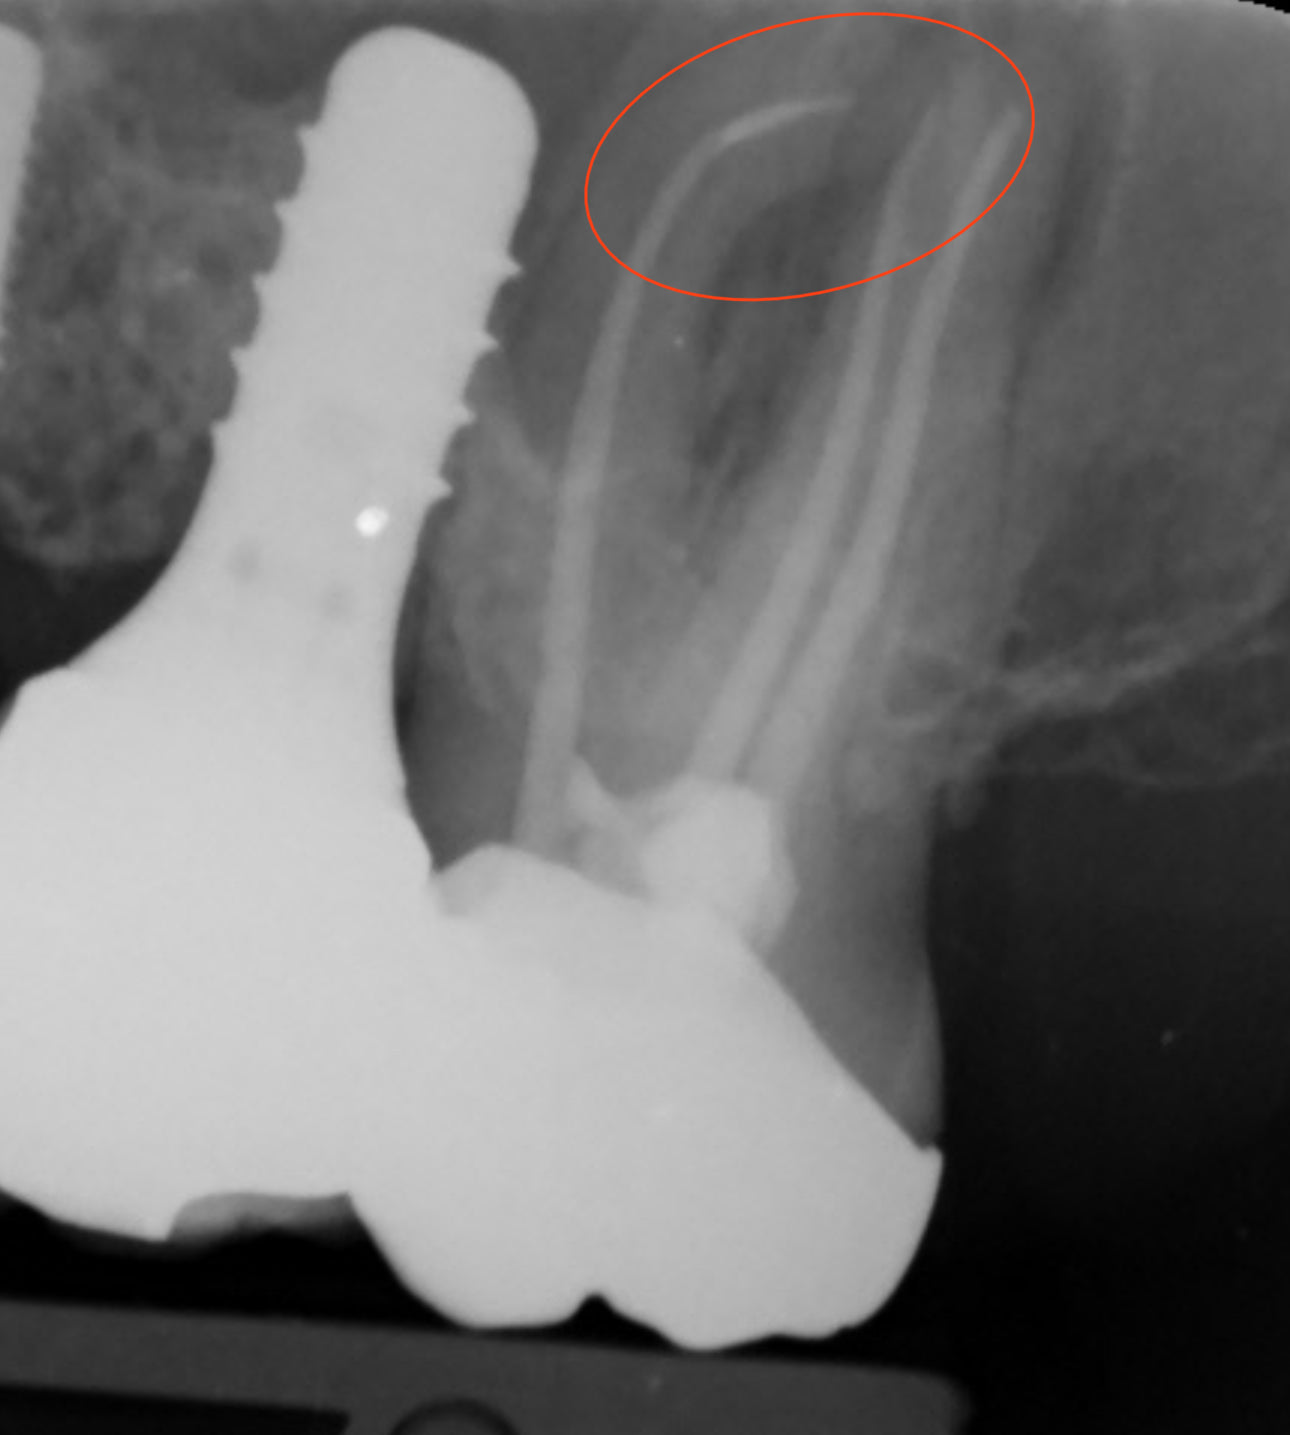

- Begin by assessing the situation clinically and radiographically.

- Confirm the presence and location of the broken file within the root canal.